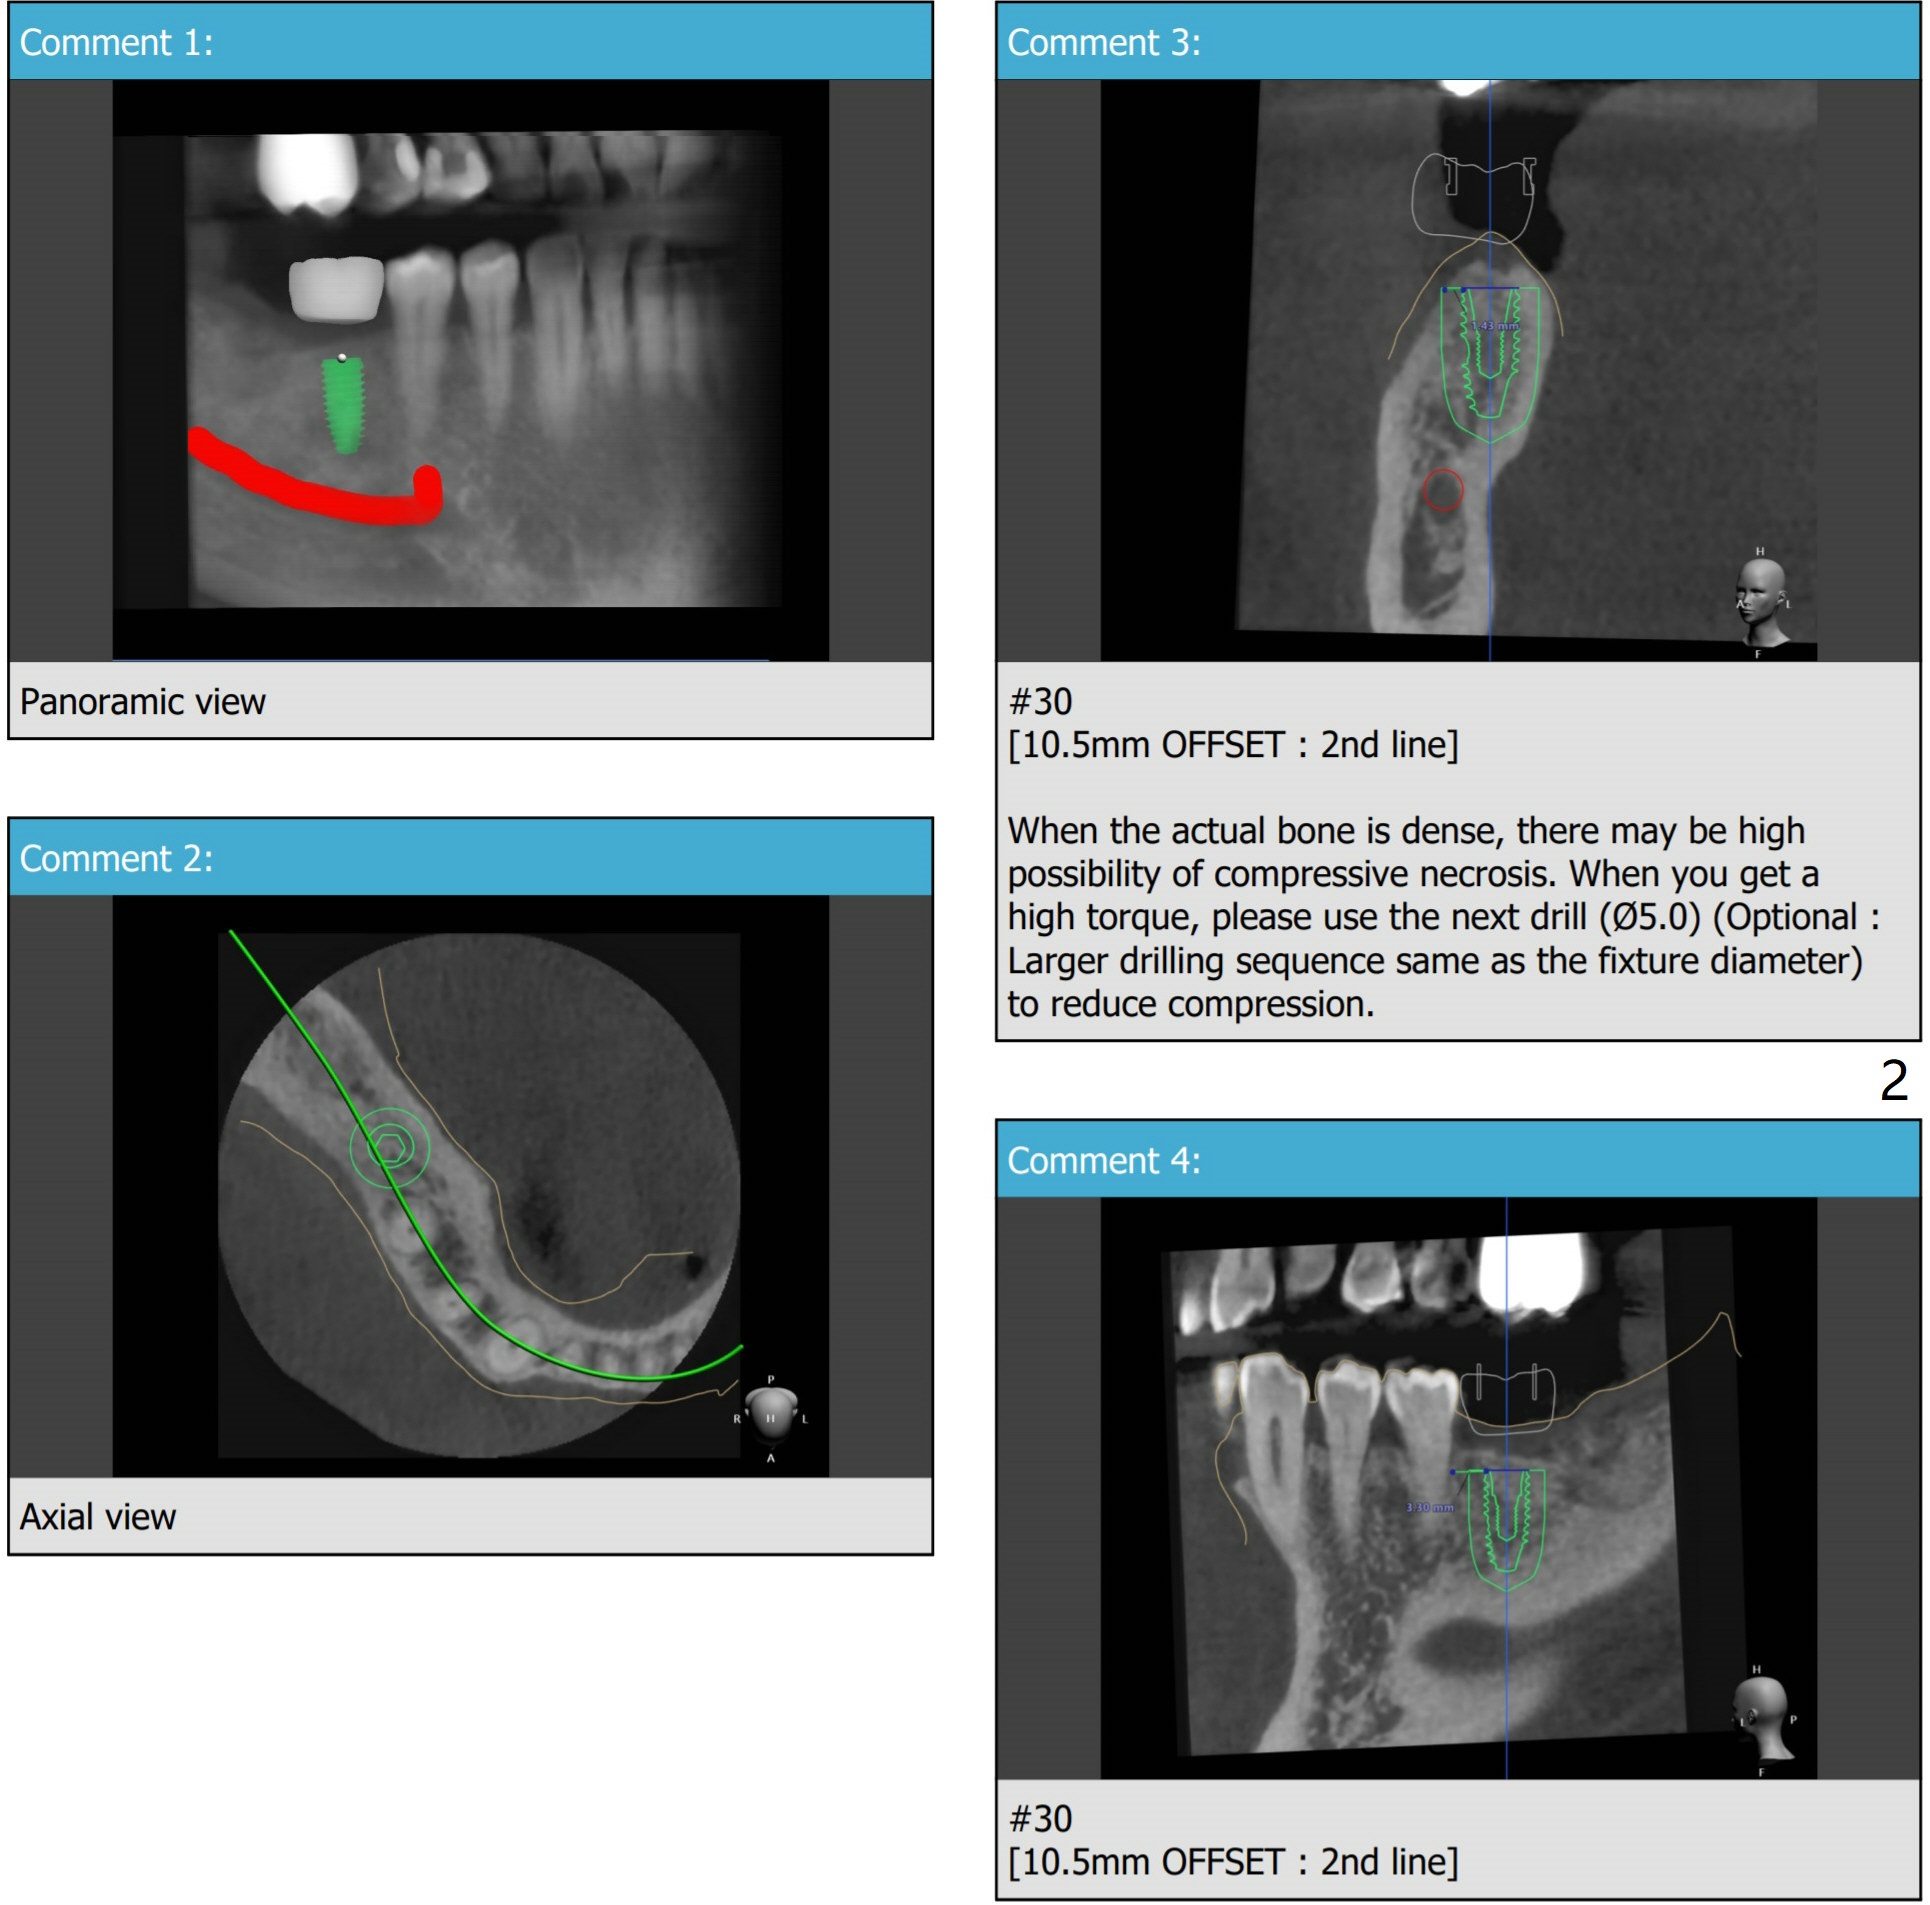

Since the bone density at #30 is high and a 4.5 mm implant is to be placed close to the very dense lingual plate (to avoid ridge split), the last drill will be 4.5 mm. In case this is over prep (torque is low), a healing screw will be used. So incision will be made. Autogenous bone will be saved and placed buccal to the implant.